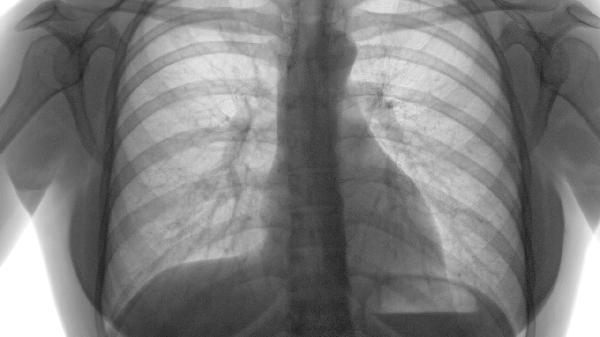

肺活量不好可能与遗传、生活习惯、疾病等因素有关,改善肺活量可以通过适度运动、呼吸训练和健康生活方式来实现。肺活量是衡量肺部健康的重要指标,低肺活量可能影响日常活动能力和整体健康,早期干预和调节有助于提升肺功能。

5、病理因素如慢性阻塞性肺病、哮喘等疾病,可能直接导致肺活量下降。针对这些疾病,及时就医、遵医嘱使用药物如支气管扩张剂、吸入性皮质激素等,可以有效控制病情,改善肺功能。